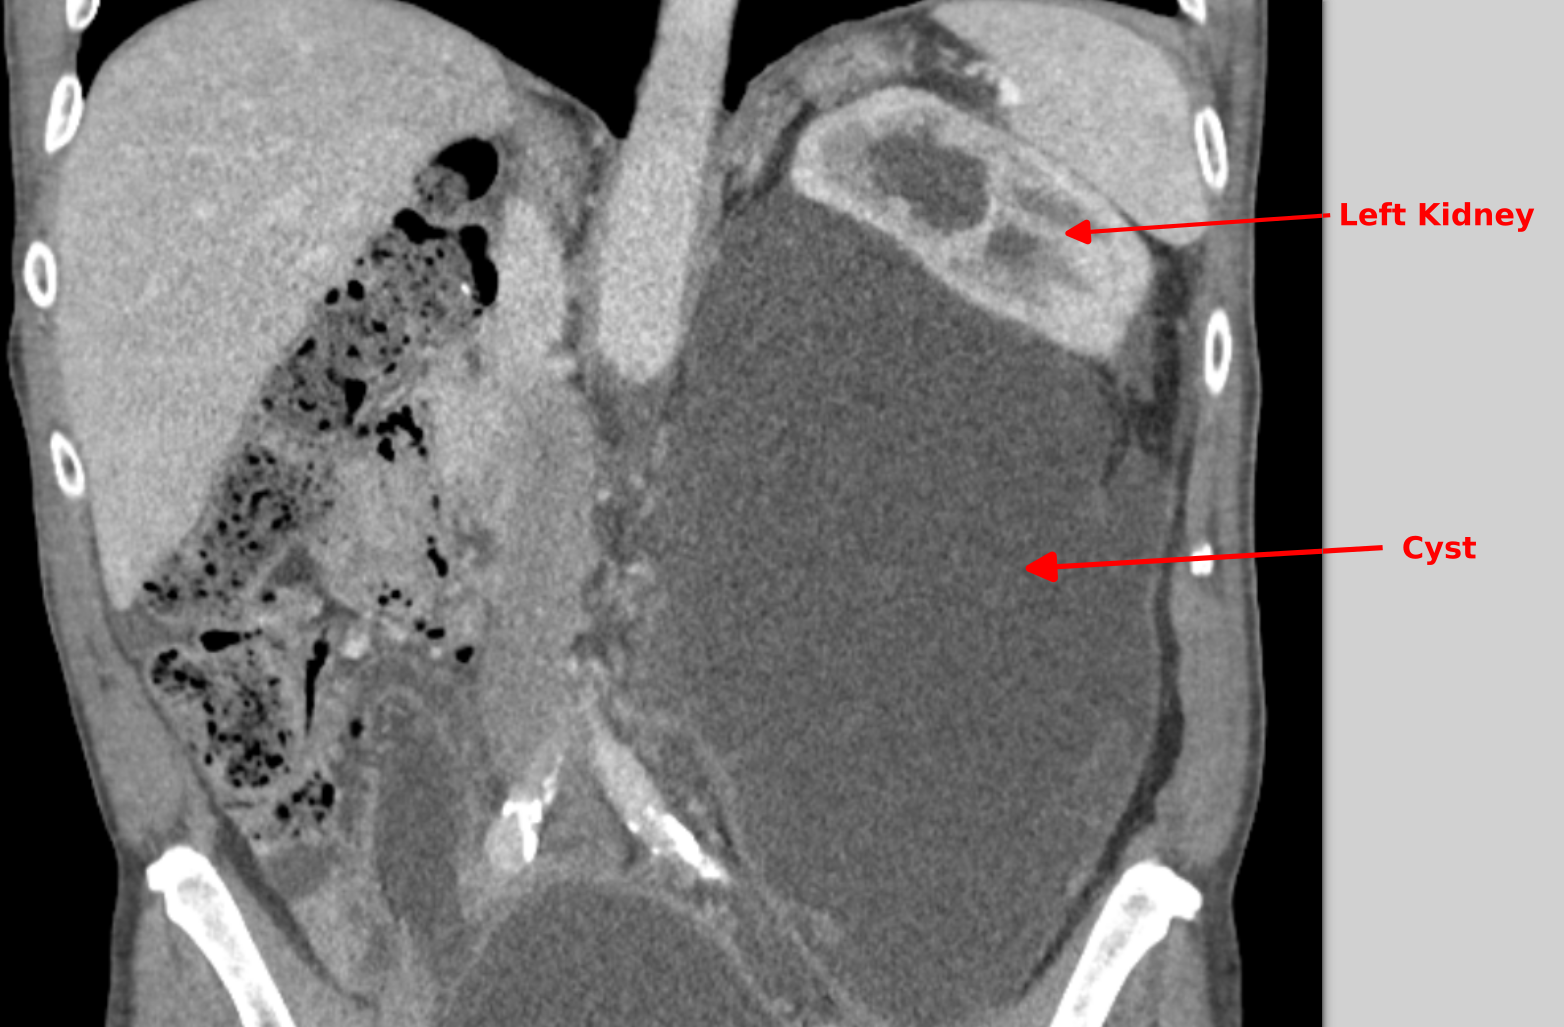

My CT-Scan

Full size is

1564 × 1027

pixels